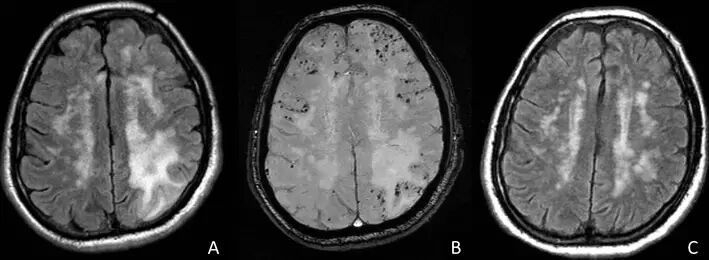

CT平扫可提示皮质下广泛低密度病灶,通常累及颞叶或额叶。几乎所有患者的MRI均异常,主要表现为T2或FLAIR上单发或多发的白质高信号,可伴水肿,病灶常为非对称性,可散在分布或融合成片或呈肿瘤样伴占位效应,灰质较少累及T2*WI上绝大多数患者存在皮质-皮质下微出血,部分患者皮质-皮质下既有微出血又有大出血,只有少数患者表现为大出血。约50%患者有脑白质疏松表现,50%患者有脑膜轻度增强。脑血管造影可见约22%患者存在轻度的双侧脑血管狭窄,主要是大脑中动脉、大脑前动脉的小分支。

(59岁男性。A:SWI上可见脑叶弥漫微出血灶;FLAIR提示皮质下双侧不对称性高信号病灶)

(68岁男性,头痛4周。A:FLAIR可见左侧顶叶大片皮质下高信号病灶;B:SWI证实双侧皮质-皮质下多发微出血;C:9月后复查病灶基本消失)